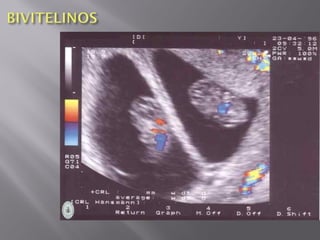

 Gemelos fraternos,bivitelinos, biovulares, son los gemelos provenientes de dos óvulos diferentes. Pueden tener el mismo sexo o no. Geneticamente diferentes. Cada gemelo tiene su propia placenta y membranas. Patologías diferentes. _Impregnación: Ruptura de un folículo con dos óvulos o dos folículos simultáneamente. La fecundación es en el mimo coito. _Súper impregnación: Ruptura de dos folículos en distinto momento. La fecundación es en distintos coitos. Súper fecundación: Mismo ciclo. Súper fetación: Distinto ciclo.